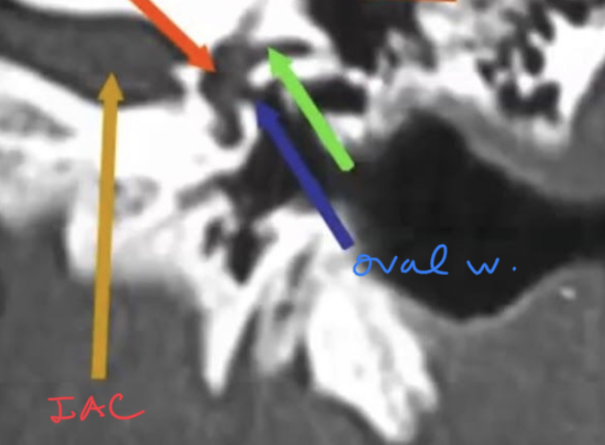

Tell the traject of the facial nerve in the skull base?

Nerves inside the IAC with subdivisions?